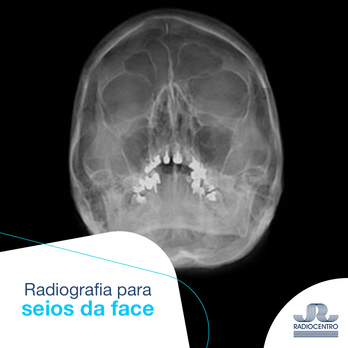

Radiografia Para Seios Da Face – Radiocentro

www.radiocentro.com.br

www.radiocentro.com.br